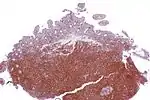

Micrograph showing mantle cell lymphoma (bottom of image) in a biopsy of the terminal ileum. H&E stain.

Micrograph of terminal ileum with mantle cell lymphoma (bottom of image). H&E stain.

Micrograph of terminal ileum with mantle cell lymphoma (bottom of image - brown colour). Cyclin D1 immunostain.